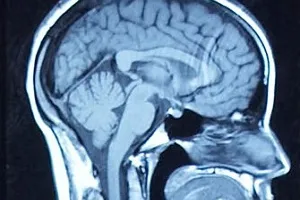

Clinician Scientist, Neuroscience

Neurosurgeon, Neurosurgery

The Ottawa Hospital

Dr. Adam Sachs is the Director of Neuromodulation and Functional Neurosurgery at The Ottawa Hospital, Associate Professor of Surgery in the Division of Neurosurgery, Associate Professor at the University of Ottawa Brain and Mind Research Institute, Associate Scientist at the Ottawa Hospital Research Institute, and Adjunct Professor of Systems and Computer Engineering at Carleton University. Prior to medical school, he completed a Bachelor of Science at McGill University in physiology and math, and a Master of Science at York University in applied mathematics researching mechanisms of human edge detection. During his neurosurgery residency at the University of Ottawa he participated in the Clinical Investigator program, performing neurophysiology and brain computer interface research in non-human primates. He was a Clinical Instructor in Functional and Spine neurosurgery at Stanford University from 2010 to 2012, where he was involved in human brain computer interface research.